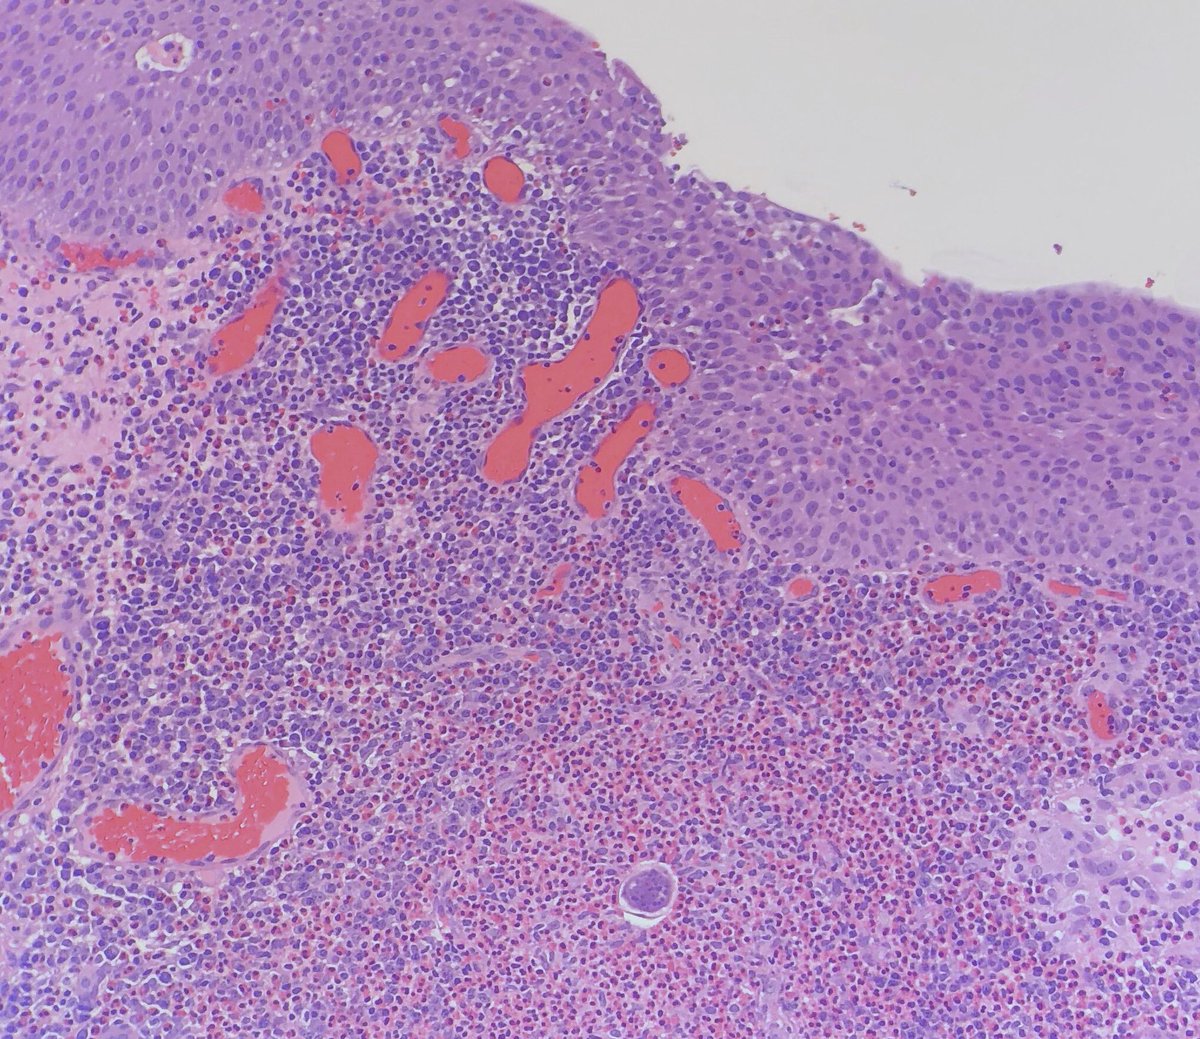

I love that! It's

#ActiveLearning and the implementation of#DigitalPathology, replacing conventional#microscope, is something new generation of students really appreciate. Changing the perception of#Pathologists at#SESAM2018#Bilbao

#MedEd@lara_pijuan@EMadrigalDOpic.twitter.com/nPY1Qe2Und -